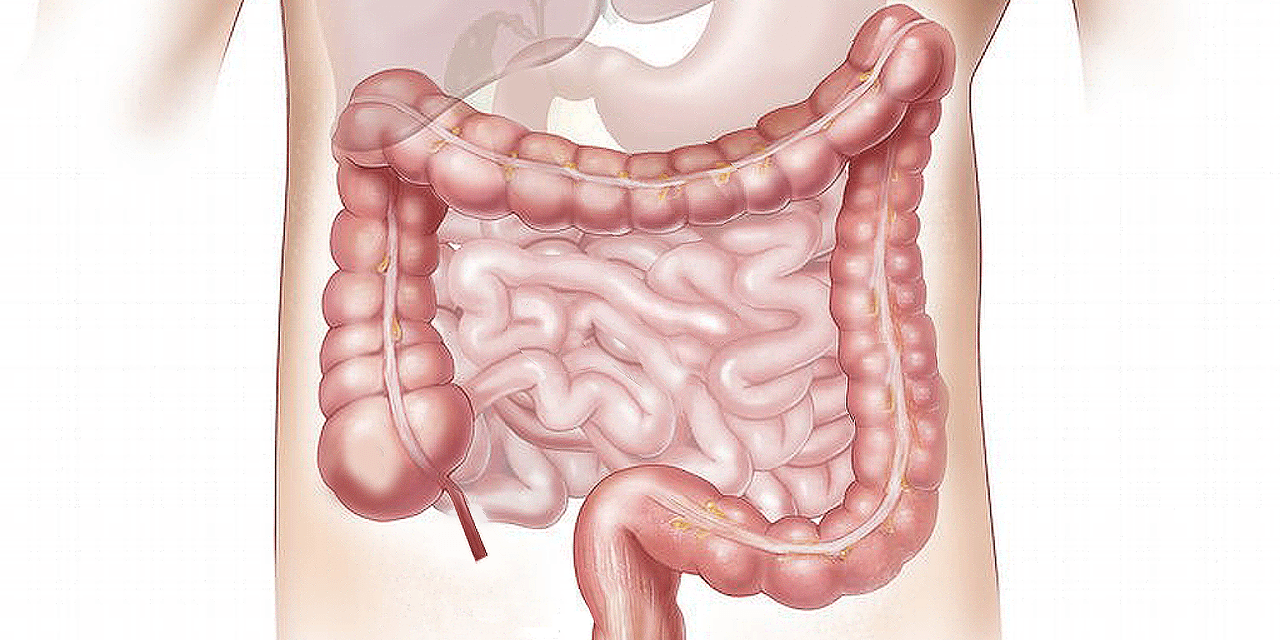

Układ odpornościowy Układ pokarmowy

Alergiczne zapalenie jelita grubego po raz pierwszy objawia się najczęściej...